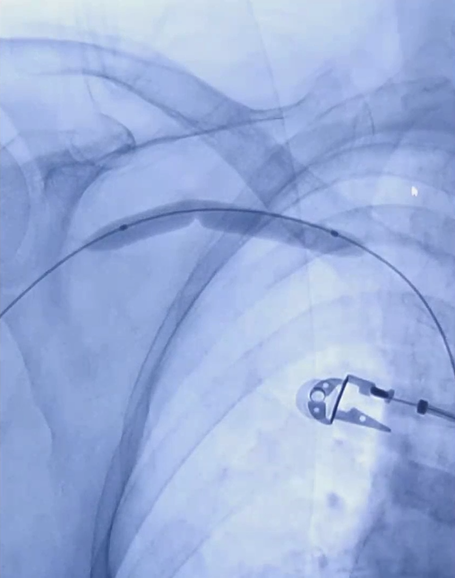

3/ 选用6mm×40mm及8mm×60mm ZENFLOW® HP(归创)球囊扩张导管依次扩张头静脉弓狭窄段;

8mm×60mm